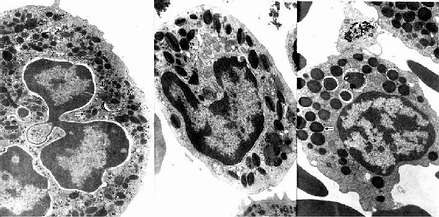

中性粒细胞的胞质染成粉红色,含有许多细小的淡紫色及淡红色颗粒,颗粒可分为嗜天青颗粒和特殊颗粒两种。嗜天青颗粒较少,呈紫色,约占颗粒总数的20%,光镜下着色略深,体积较大;电镜下呈圆形或椭圆形,直径0.6~0.7μm,电子密度较高(图5-4,5-5),它是一种溶酶体,含有酸性磷酸酶和过氧化物酶等,能消化分解吞噬的异物。特殊颗粒数量多,淡红色,约占颗粒总数的80%,颗粒较小,直径0.3~0.4μm,呈哑铃形或椭圆形,内含碱性磷酸酶、吞噬素、溶菌酶等。吞噬素具有杀菌作用,溶菌酶能溶解细菌表面的糖蛋白。

2.嗜酸性粒细胞 嗜酸性粒细胞(eosinophilic granulocyte,eosinophil)占白细胞总数的0.5%-3%。细胞呈球形,直径10~15μm,核常为2叶,胞质内充满粗大(直径0.5~1.0μm)、均匀、略带折光性的嗜酸性颗粒,染成桔红色(图5-2)。电镜下,颗粒多呈椭圆形,有膜包被,内含颗粒状基质和方形或长方形晶体(图5-4,5-5)。颗粒含有酸性磷酸酶、芳基硫酸酯酶、过氧化物酶和组胺酶等,因此它也是一种溶酶体。

3.嗜碱性粒细胞 嗜碱性粒细胞(basoophilic granulocyte,basophil)数量最少,占白细胞总数的0~15。细胞呈球形,直径10-12μm。胞核分叶或呈S形或不规则形,着色较浅。胞质内含有嗜碱性颗粒,大小不等,分布不均,染成蓝紫色,可覆盖在核上(图5-2)。颗粒具有异染性,甲苯胺蓝染色呈紫红色。电镜下,嗜碱性颗粒内充满细小微粒,呈均匀状或螺纹状分布(图5-4,5-5)。颗粒内含有肝素和组胺,可被快速释放;而白三烯则存在于细胞基质内,它的释放较前者缓慢。肝素具有抗凝血作用,,组胺和白三烯参与过敏反应。嗜碱性粒细胞在组织中可存活12-15天。

图5-4 三种粒细胞超微结构模式图

图5-5 人三种粒电镜像 ×17800

左图:中性粒细胞(白求恩医科大学尹昕、朱秀雄教授供图)

中图:嗜酸性粒细胞 左图:嗜碱性粒细胞

↑特殊颗粒,()嗜天青颗粒